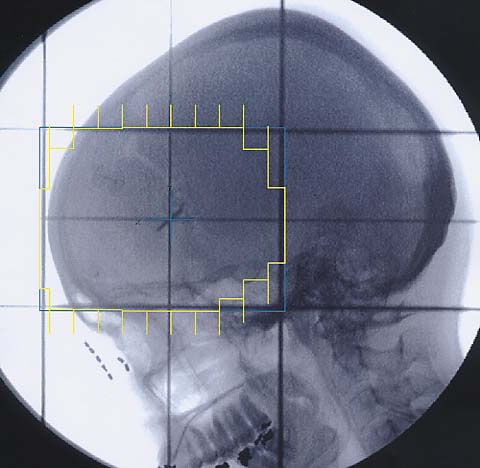

Hirntumore: Simulationsbild